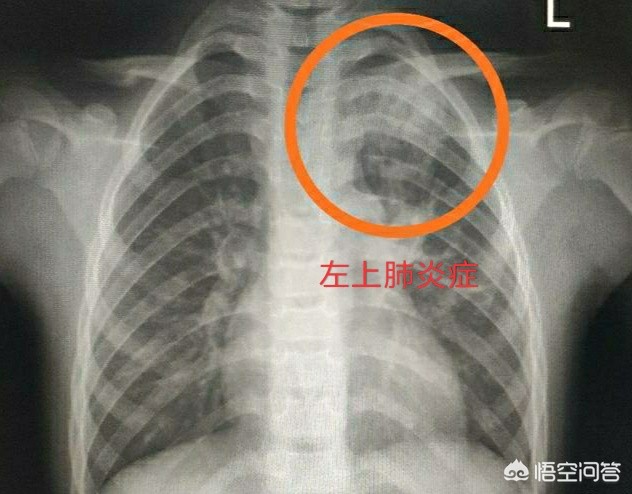

先来看一张小儿肺炎治疗前后对比的图像:典型的小儿肺炎,治疗一周后复查胸片。 可以看到左上肺的大片炎症,抗炎治疗一周后明显吸收消散。宝宝如果出现了明显高热,持续的咳嗽咳痰一定要及时就诊,防止发生大叶性肺炎,继发其他系统的问题。